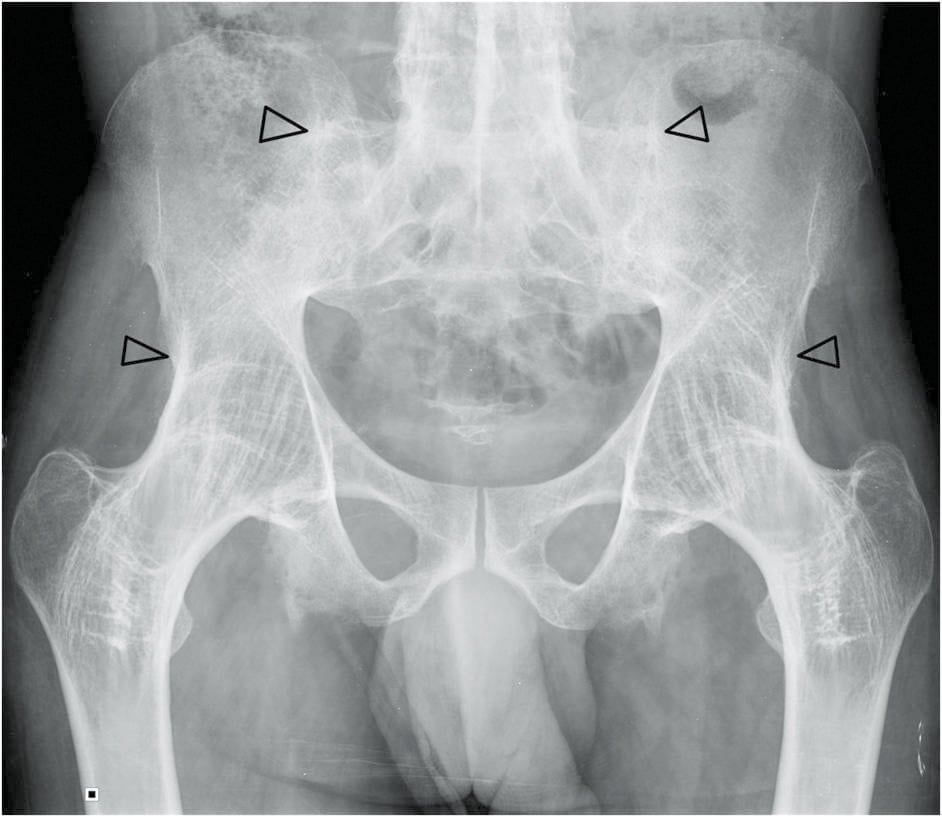

Для диагностирования заболевания используются инструментальные методы: рентгенография, КТ, МРТ. Консервативное лечение анкилоза не проводится. Оперативное вмешательство (остеотомия, артропластика, эндопротезирование сустава) показано пациентам при патологии в функционально неблагоприятном положении. После диагностирования анкилоза коленного, плечевого, тазобедренного суставов больному дают группу инвалидности.

Анкилоз коленного, плечевого, тазобедренного суставов выявляется при проведении инструментальных исследований по сужению и прерывистым контурам суставной щели или ее полному сращению. При диагностировании используются:

- рентгенография;

- компьютерная томография;

- магнитно-резонансная томография.

Ультразвуковое исследование коленных, плечевых, тазобедренных суставов проводится только для обнаружения начальной стадии заболевания, а также для оценки состояния околосуставных структур — мышц, мягких тканей, нервов, кровеносных и лимфатических сосудов. Общий анализ крови и мочи позволяет установить наличие процесса воспаления и его интенсивность. Обязательно берется образец экссудата для обнаружения инфекционных агентов, их видовой принадлежности и чувствительности к антибиотикам.